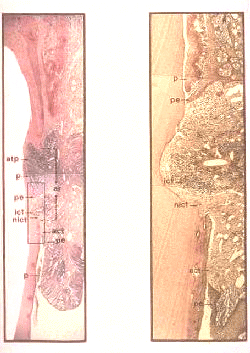

Sección buco-lingual del periodonto en un diente molar de un perro con enfermedad periodontal naturalmente ocurriendo. El epitelio de unión se localiza hacia el cemento de la raíz. La terminación apical  del epitelio de unión desaparece exponiendo el tejido conjuntivo. La razón para esta variante de destrucción periodontal es la ocurrencia de las áreas vecinas de infección subgingival.